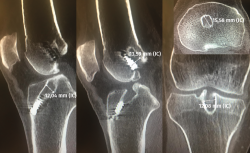

Figura 1. Imagen radiológica que permite identificar una técnica de reconstrucción transtibial o “monotúnel” (izquierda) respecto a una técnica anatómica (derecha).

El estudio radiológico recomendado debería incluir proyecciones anteroposteriores y laterales, axiales de rótula, telemétricas de la extremidad inferior y también en posición de Schuss (en carga y con unos 30° de flexión de la rodilla). La radiología simple va a permitir identificar qué técnica quirúrgica se realizó inicialmente y qué material se utilizó para la fijación (Figura 1). La proyección en Schuss permite observar si existen cambios degenerativos en los compartimentos femorotibial interno o externo de la rodilla de forma más precisa que con la radiología simple en decúbito supino. Finalmente, la radiografía telemétrica de las extremidades inferiores va a permitir conocer el eje mecánico de la extremidad. La existencia de deformidades en el plano coronal se ha asociado a un incremento de la solicitación mecánica del LCA y también del riesgo de rotura de la plastia (Figura 2)(21).